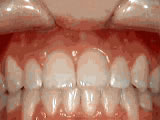

Deep Overbite Correction

Adult patient (age 25) underwent braces and jaw surgery for two years to correct a severe overbite — early treatment could have prevented surgery.

Deep overbite - Lower front teeth bite into palate before Deep overbite - Lower front teeth bite into palate after